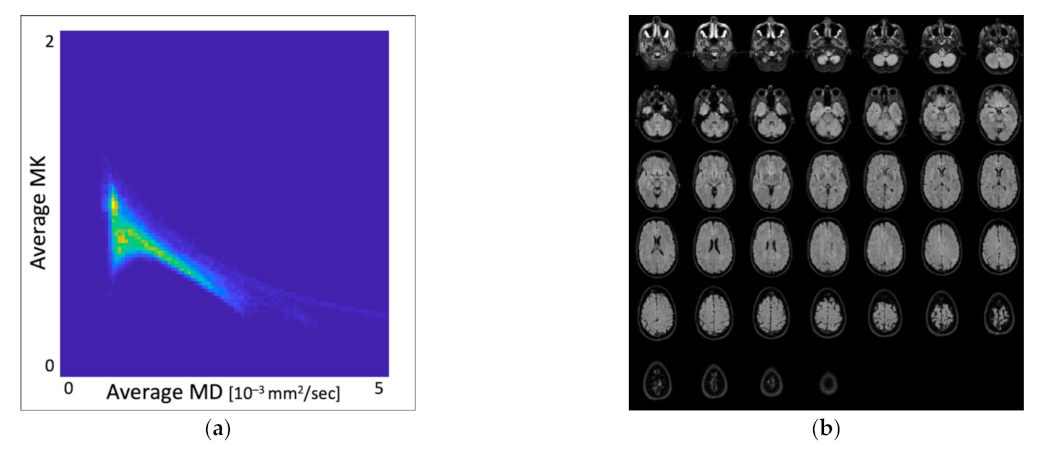

3.1. Distribution of MK and MD Values in Whole-Brain DKI Maps